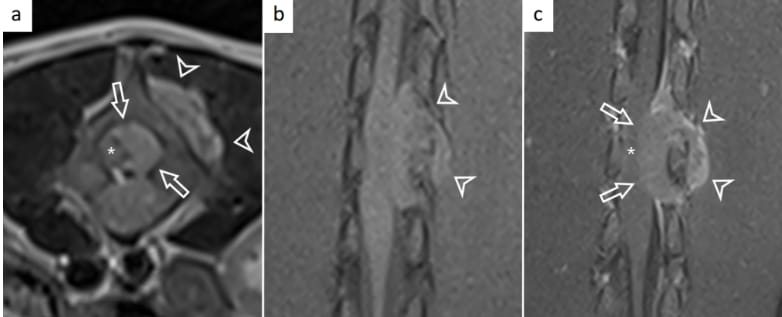

Magnetic resonance imaging findings of the lumbar spine. Transverse T2-weighted image at the level of the L4 vertebra (a) and dorsal T1-weighted image on the level of the spinal cord pre-contrast (b) and post gadolinium contrast (c) showing a confirmed extradural mass encompassing the left pedicle of L4. The mass appears hyperintense on T2-weighted sequences (a), isointense to the spinal cord on T1-weighted sequences (b), and moderately, heterogeneously contrast enhancing with meningeal enhancement “dural-tail”-sign (c). The mass extends into the vertebral canal (white arrows) and left dorsolateral (white arrowheads). The mass displaces and compresses the spinal cord towards the right (asterisk)

MRI revealed a 2.8 x 1.3 x 1.1 cm, well-defined, extradural mass centered at L3–L4, displacing and compressing the spinal cord. The mass extended dorsolaterally with evidence of vertebral bone destruction. Post-mortem confirmed an epidural round cell sarcoma with osseous and para-spinal soft tissue involvement, but without dural or muscular invasion. Histologically, the tumor consisted of pleomorphic round cells with high mitotic activity. IHC was negative for all tested markers except for ~14% Ki-67 positivity, confirming a diagnosis of poorly differentiated round cell sarcoma.